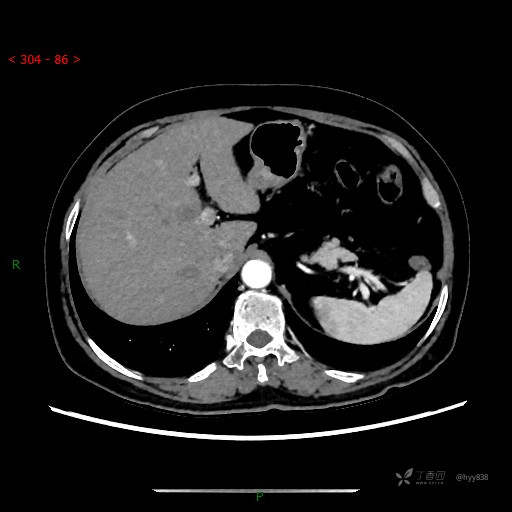

增强动脉期